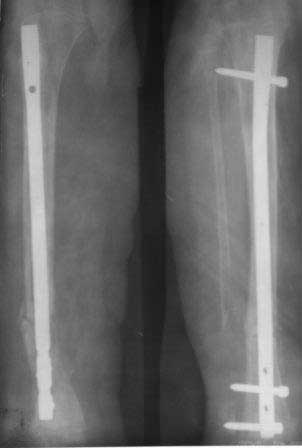

Девочка 2005г.р. В середине 2008 г падает с велосипеда с дедом, возможно был перелом н/з костей левой голени, лечение у знахаря-табиба, но ребенок не смог бегать, часто падал, начал хромать. Май 2009г. обратились к нам, установлен д-з « вялоконсолидирующаяся перелом н/з б/берцовой кости, несросшийся перелом м/берцовой кости со смещением по ширине». Мы решили гипсовая повязка и ходьба с нагрузкой, но по категорическому требованию родителей исправить деформацию м/берцовой кости, произвели операцию ( на свою голову )»о/ репозиция и и/м фиксация спицами м/берцовой кости». Теперь началась самая интересная история! Ч-з недели две в обл. п/о раны м/берцовой открылась свищ с кровянистым выделением, гноя не было, на р-грамме лизис концов отломков м/берцовой кости, к-рый начал прогрессировать, консультирована онкологами, цитология, с подозрением направлена в центральные институты, сделана КТ, онкологическое исключили, в августе попали в остеомиелитический центр, где произведена резекция м/б на протяжение 6-7см, все зажило и выписали (снимок-1). 2010г в мае повторно получила травму, наложена гипсовая повязка (снимок-2) и через 1-2 месяца в одном из центральном институте произведена КДО аппаратом Илизарова , который снят ч-з три месяца (снимок-3) и долго ходила на костылях-мать заставила, как начала наступать, появилась деформация, заказали ортез и так ходила, но деформация прогрессировала, Обратилась к нам в апреле 2012г,(снимок-4) произведена постепенная коррекция на аппарате, и замена на БИОС 01.03.12г плечевым гвоздем, ЭОП нет, поэтому осталась несколько антекурвация (снимок-5), ребенок ч-з неделю начала ходить.Повторный осмотр 22.06.12г- деформация усиливается, за три месяца сращение очень слабое.(снимок-6). (Жаль что многие р-снимки не сохранились, мать обещала хотя бы часть найти)!